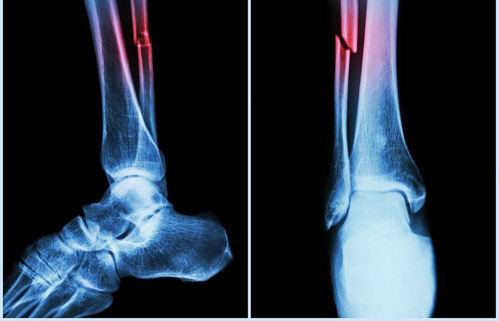

The automated system analyses vertebral fracture assessment (VFA) images to detect abdominal aortic calcification (AAC) – a key marker linked to heart attacks, strokes, and falls.

Further research by ECU’s Marc Sim revealed that AAC is not only a cardiovascular risk indicator but also a strong predictor of falls and fractures. In fact, AAC outperformed traditional fall risk factors like bone mineral density and past fall history.

“The higher the calcification in your arteries, the higher the risk of falls and fractures,” Sim said, adding clinicians typically overlook vascular health in fall assessments, and this algorithm changes that.

“Our analysis uncovered that AAC was a very strong contributor to fall risks and was actually more significant than other factors that are clinically identified as fall risk factors.”

Sim said that the new machine algorithm, when applied to bone density scans, could give clinicians more information about the vascular health of patients, which is an under-recognised risk factor for falls and fractures.